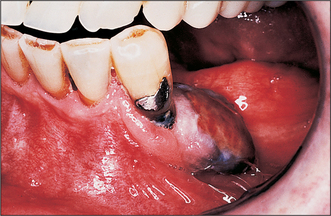

Colour

Colour will distinguish between fibroepithelial polyps (pink) (Fig. 8.1) and the white rough cauliflower presentation of viral papillomas (warts) (Fig. 8.2). Mucous cysts tend to be translucent with a bluish colour (see Figs 14.7, 14.8) and haemangiomas and ‘venous lakes’ (Fig. 8.3) dark blue. Pyogenic granulomas (Fig. 8.4) and giant-cell epulides (Fig. 8.5) normally present as maroon/red.

Fig. 8.5 Peripheral giant-cell granuloma, lower premolar region.